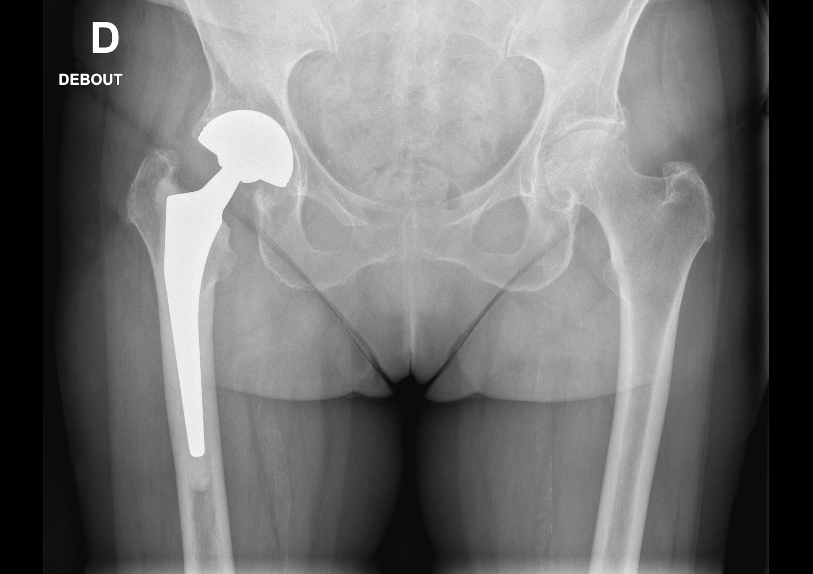

La prothèse totale de hanche est une intervention chirurgicale qui consiste à remplacer l’articulation de la hanche par des pièces artificielles de forme et de taille similaires aux surfaces osseuses usées. Elle comporte généralement trois éléments : une cupule métallique fixée dans le bassin, une tige insérée à l’intérieur du fémur et une tête sphérique qui s’emboîte dans la cupule, recréant ainsi l’articulation de la hanche. Cette opération est le plus souvent proposée aux patients souffrant de destruction du cartilage de la hanche, par exemple en raison d’une arthrose (usure du cartilage) avancée, d’une fracture du col du fémur ou d’autres maladies de la hanche qui provoquent des douleurs et une limitation importante des mouvements. En d’autres termes, lorsqu’une hanche est très abîmée et douloureuse malgré les traitements médicaux, la pose d’une prothèse permet de soulager la douleur et de retrouver une meilleure mobilité.

Technique chirurgicale

L’intervention se déroule sous anesthésie (générale ou rachianesthésie selon le contexte). Le chirurgien pratique une incision sur le côté (voie postérieure) ou l’avant de la hanche (voie antérieure), puis accède à l’articulation abîmée dans des conditions d’asepsie strictes (salle d’opération stérile). La partie supérieure du fémur, dont le cartilage est détruit, est coupée et retirée. Le chirurgien prépare ensuite le fémur en y creusant un espace pour introduire la tige fémorale de la prothèse. De même, la cavité cotyloïde (logée dans le bassin) est préparée afin d’y fixer la cupule artificielle. Une fois ces préparations effectuées, les éléments de la prothèse (tige fémorale avec sa tête sphérique, et cupule) sont implantés. Ils peuvent être fixés soit par impaction directe, soit à l’aide de ciment chirurgical, selon le type de prothèse et la qualité de l’os. Le chirurgien assemble ensuite la tête fémorale dans la cupule, reconstituant ainsi une nouvelle articulation de hanche. En fin d’intervention, les muscles et tissus autour de l’articulation sont remis en place et la peau est refermée avec des fils, d’agrafes ou bien de colle biologique. L’opération dure en moyenne une heure. Après la chirurgie, un pansement est appliqué sur la cicatrice et des soins post-opératoires (antidouleurs, anticoagulants préventifs, etc.) sont mis en place.